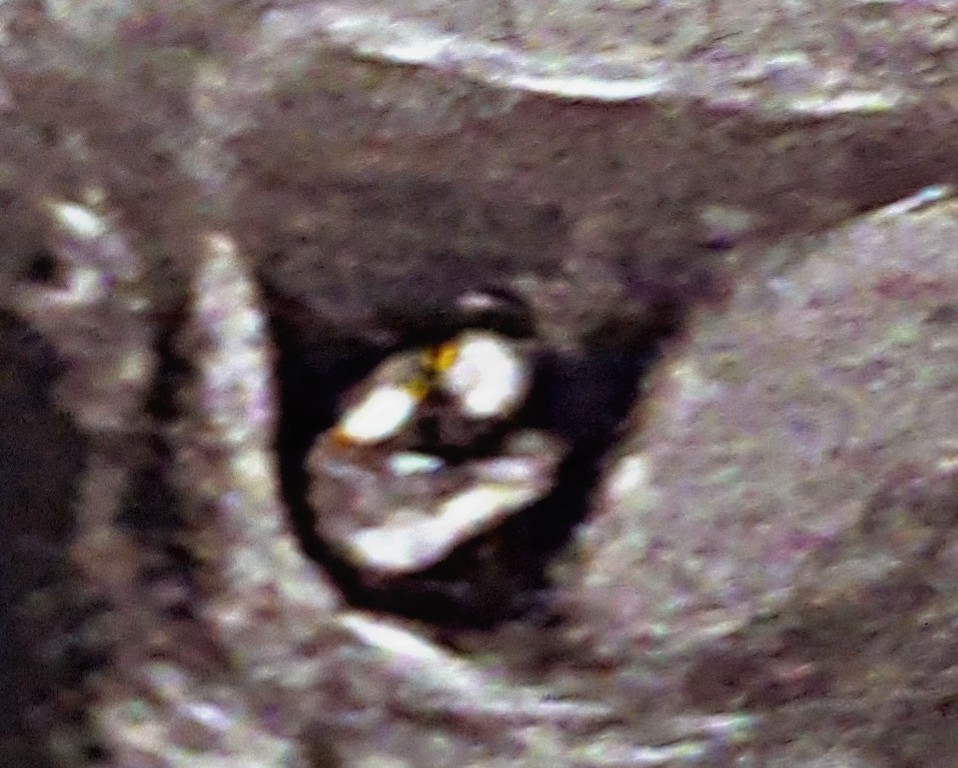

So we already have 4 boys and I am expecting again in August! The following scan pics were taken at 12+3.

My gut tells me this is a boy - however the majority of time on screen nub looked totally straight so these pics surprised me. Plus with all 4 other boys at this point potty shot was already really obvious whereas this looks totally different.

What do you think? Is there the smallest hope this is a girl or do I have to face being manager to my own 5 a side football team... that's soccer if you are in USA 😂🤣